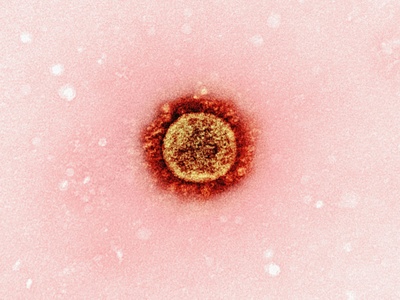

COVID-19

COVID-19 is caused by SARS-CoV-2, commonly producing fever, cough, fatigue and loss of smell; severe cases cause pneumonia and long-term symptoms. Global since 2019; spreads by respiratory routes. Vaccines and masks reduce risk; treatments and antivirals available for high-risk patients.